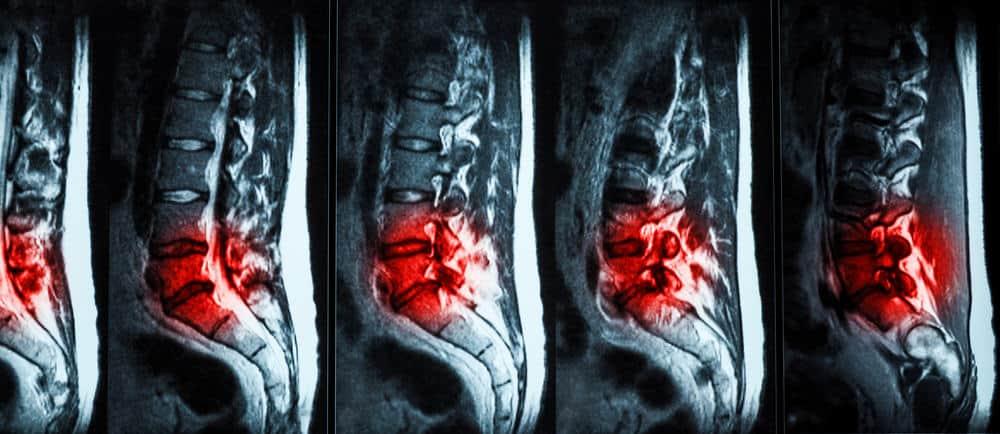

မြန်မာနိုင်ငံမှာ အရိုးအကြောခွဲစိတ်မှု ဌာနက အလုပ်များတဲ့ ဌာနပါ။ နေ့တိုင်း ကားမတိုက်တဲ့ရက်၊ ဆိုင်ကယ်မမှောက်တဲ့ရက်၊ ချော်မလဲတဲ့ရက်ရယ်မှ မရှိပဲလေ။ တစ်ခုခု ပြင်းပြင်းထန်ထန် ထိခိုက်မိလို့ အရိုးထိသွားပြီလား မသိဘူးဆို ဒီဌာနကိုပဲ ရောက်ကြလာပါတယ်။ အရိုးအကြောခွဲစိတ်မှု ဆိုတာ အရိုးအကြောခွဲစိတ်မှု ဆိုတာ အထူးပြုခွဲစိတ်မှု တစ်ခုပါ။ အရိုးနဲ့ ပတ်သက်တဲ့ ရောဂါတွေ (အရိုးအဆစ်၊ တွယ်ဆက်တစ်ရှူးတွေ ဖြစ်တဲ့ အရွတ်တွေ၊ အရွတ်တွဲတွေ) အားလုံးကို ကုသမှု ပေးပါတယ်။ သာမန်အဆစ်လွဲတာကစလို့ ကျောရိုးခွဲစိတ်မှုတွေ၊ ပေါင်ရိုးအစားထိုးမှုတွေအထိ ပါပါတယ်။ မတော်တဆ ဖြစ်တာကနေ စလို့ ရောဂါတွေအထိ ပါဝင်တာကြောင့် အရေးပေါ်ကုသမှု လိုသလို တခြားရောဂါတွေကို အေးဆေးရက်ချိန်းပြပြီးမှ ကုရတာလည်း ဖြစ်နိုင်ပါတယ်။ အရိုးအကြောခွဲစိတ်မှုက အင်မတန်ကျယ်ပြန့်ပါတယ်။ ဖြစ်တဲ့ ဝေဒနာပေါ်မူတည်ပြီး ခွဲစိတ်မှု အကြီးအသေး၊ ပြန်ကောင်းဖို့ ကြာချိန်တွေ ကွာနိုင်ပါတယ်။ အရိုးအကြောခွဲစိတ်မှုမှာ […]